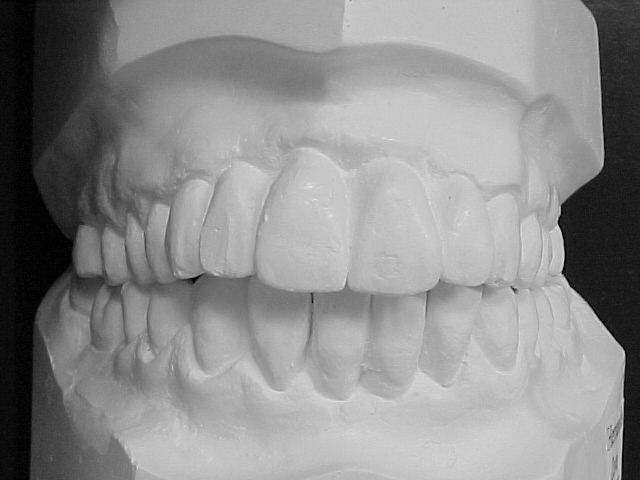

Modelos de estudo antes do tratamento

|

Modelos em gesso após o tratamento